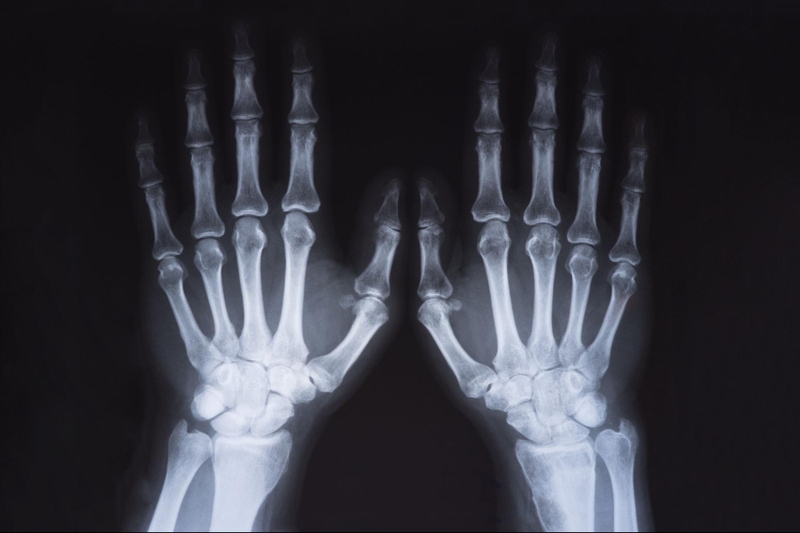

Chụp X quang bàn tay là kỹ thuật thường được các bác sĩ chỉ định thực hiện đối với bệnh nhân đang gặp vấn đề ở bàn tay. Vậy trong trường hợp cụ thể nào thì cần áp dụng và quy trình tiến hành bao gồm những gì?

Chụp X quang bàn tay là kỹ thuật mà bác sĩ sẽ sử dụng tia X để chiếu xuyên qua bàn tay nhằm ghi lại hình ảnh giải phẫu của bàn tay một cách chính xác và rõ nét. Đây được xem là kỹ thuật có quy trình thực hiện khá đơn giản, thời gian thực hiện nhanh chóng, chi phí hợp lý, phù hợp với đại đa số người bệnh. Hơn nữa, kết quả thu được giúp bác sĩ rất nhiều trong việc phát hiện sớm các bệnh lý từ nhẹ đến nặng ở bàn tay, thậm chí cả những bệnh nguy hiểm như khối u trong xương, tiêu xương hoặc ung thư xương.

Cuối cùng, người bệnh sẽ nhận được kết quả chụp X quang bàn tay và được bác sĩ đưa ra kết luận chẩn đoán bệnh. Kết quả ảnh trên phim chụp cần phải thỏa đủ các điều kiện sau đây: